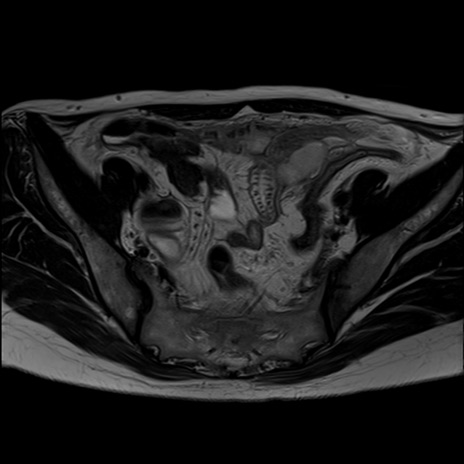

症例39 T2WI(横断像)

MRI(4日後)